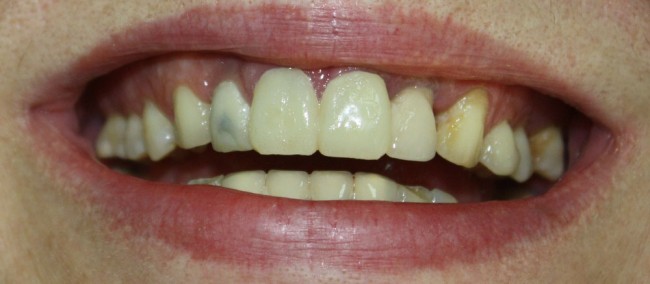

Около трёх лет назад к нам в клинику обратилась пациентка Мария, на момент обращения ей было 45 лет. Её беспокоила ситуация с передними резцами:

В ходе беседы она рассказала, что лечит эти зубы всю сознательную жизнь — их депульпировали («удалили нерв») из-за последствий травмы еще в школьном возрасте, и после этого каждые несколько лет (а то и чаще) ей приходилось перелечивать каналы, менять коронки, вкладки и т. д.

В результате, зубы приобрели очень уж нездоровый вид (см. фото выше). Вдобавок, всё усугубилось существенным снижением качества жизни — коронки и вкладки из зубов постоянно выпадают, десна вокруг них кровоточит при чистке…. Кроме того, Марию не покидает ощущение того, что эти зубы могут просто вывалиться в самый неподходящий момент. Именно это заставило её обратиться в нашу клинику.